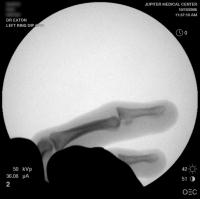

Intraoperative fluoros: The injury, reconstruction through a bayonette exposure, stable reduction.